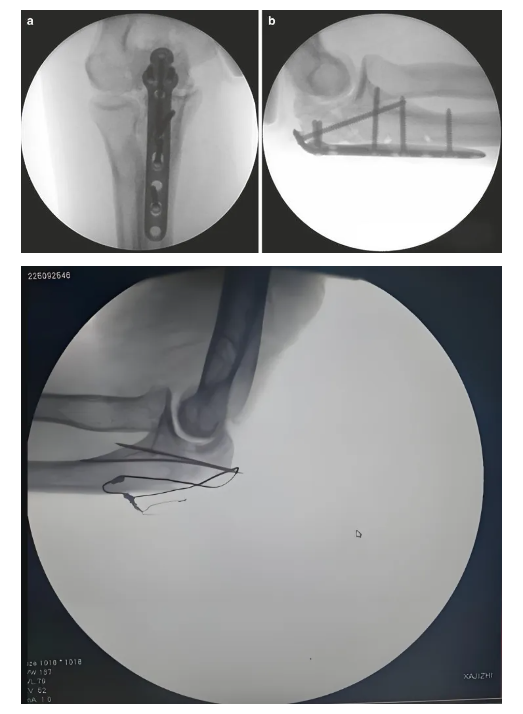

張力帶固定(ding)技術

確認骨折穩定性(xing)及關節(jie)活(huo)動(dong)度,包括旋前(qian)旋后(supination-pronation)活(huo)動(dong);排除克(ke)氏針穿入肱尺關節(humeroulnar)或(huo)橈尺關節(radioulnar joint)的可(ke)能性;術后(hou)影像學需(xu)顯示骨折復位良好、內固定位置(zhi)正(zheng)確。

鋼板內(nei)固定

術(shu)后(hou)圖片

金屬纜(lan)索系統

鋼板內固定系(xi)統